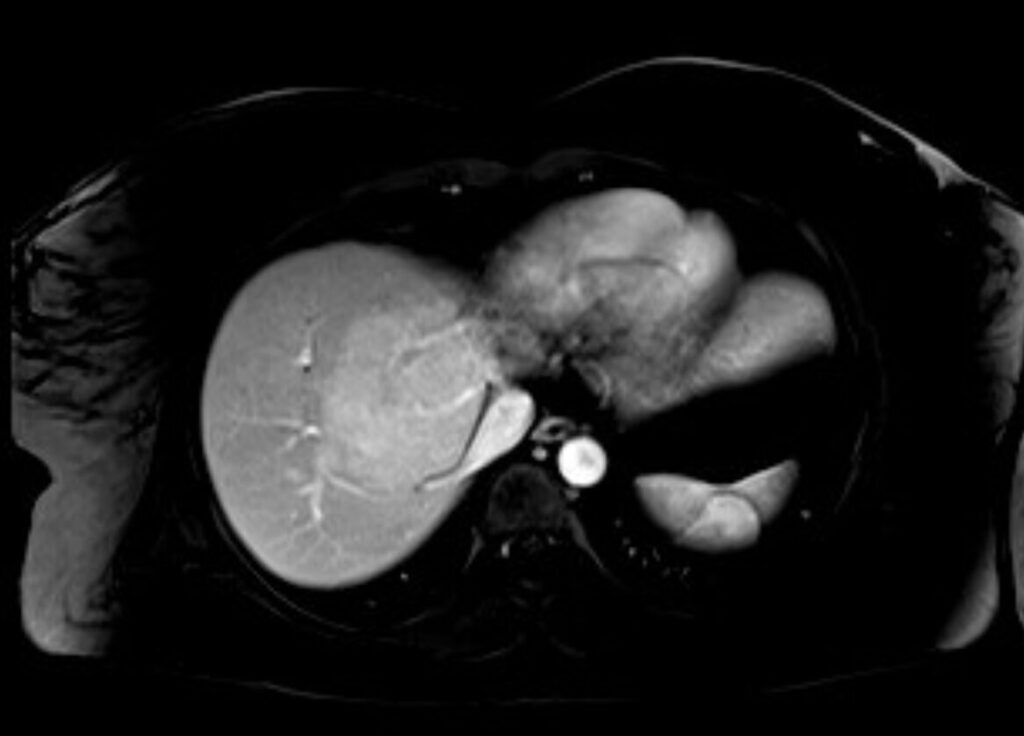

IPERPLASIA NODULARE FOCALE (FNH)

- Seconda lesione epatica benigna per frequenza, dopo l’angioma.

- Ha scarsa dipendenza dagli estrogeni, non è evolutiva e non ha rischio di emorragia per cui non è indicata l’asportazione chirurgica.

- Nel 60% dei casi presenta una cicatrice fibrosa centrale con setti a raggiera.

Aspetto RM

- Allo studio dinamico è caratterizzata da un enhancement arterioso omogeneo con isointensità tardiva (cicatrice centrale iperintensa).

- In fase epatospecifica l’enhancement permane perchè l’FNH è composto da epatociti (a differenza dell’adenoma che tende a diventare ipointenso rispetto al parenchima epatico normale).